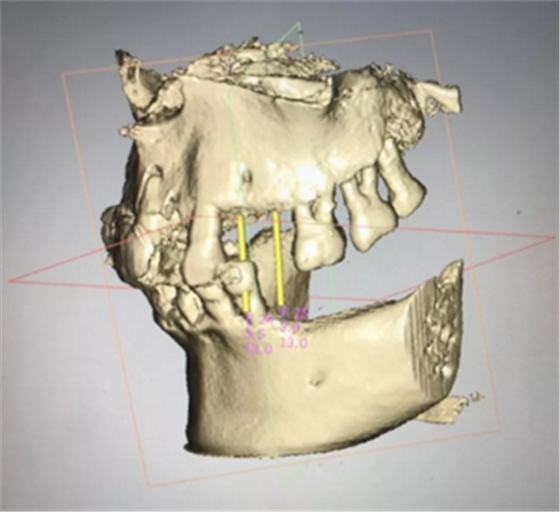

術(shù)前分析,患者上頜骨條件良好。

通過(guò)種植導(dǎo)板軟件系統(tǒng)進(jìn)行種植體模擬植入,制定種植手術(shù)方案